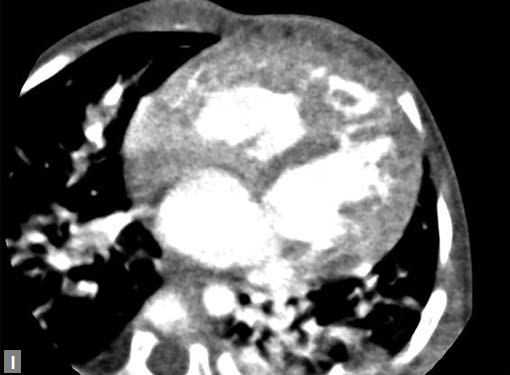

The most common mass lesion in heart is thrombus. Postinfarct clot is common in LV apex. Postinfarct aneurysm of LV may have clot. Rheumatic mitral valve disease with AF has left atrial (LA) appendage thrombus. Large one can extend to body of thrombus. Patients with arrhythmogenic right ventricular dysplasia (ARVD), sarcoidosis can have thrombus in right ventricle. SVC and IVC thrombus can extend to right atrium. Long-standing catheters can be source of thrombus in innominate veins and SVC.

Clots are more likely to have calcific foci (Figs 21I to K) within when they are long standing. Neoplasms with signifi cant neoangiogenesis show discernible contrast enhancement.

Mass lesion in left atrium with ball valve movement is a myxoma (Fig. 21L). Most commonly located near fossa ovalis of interatrial septum (IAS). Multiple myxomas are seen in

Carney’s complex. Calcification may be present. LA myxomas are pedunculated and RA ones are generally sessile.

Tiny soft tissue density lesions in relation to aortic valve represent fibroelastomas. These small lesions cannot be detected many a time and transesophageal echo has better sensitivity. Myxoma can occur in RA and can cause tumor emboli in pulmonary arteries. A fat containing lesion with Hounsfield units ranging in −50 to −100 suggests a lipoma. Lipomatous hypertrophy of IAS can be diagnosed efficiently by radiologist both on CT and MRI. Sarcomas are infiltrative in nature.

More common are metastatic lesions (Fig. 21M). Primary neoplasms can be located in breast, lungs or kidneys. Melanoma is notorious to metastasize extensively including heart.

Follicular carcinoma of thyroid, glomus jugulare can extend to RA through venous structures. Pericardial effusion accompanies many of these metastatic tumors.